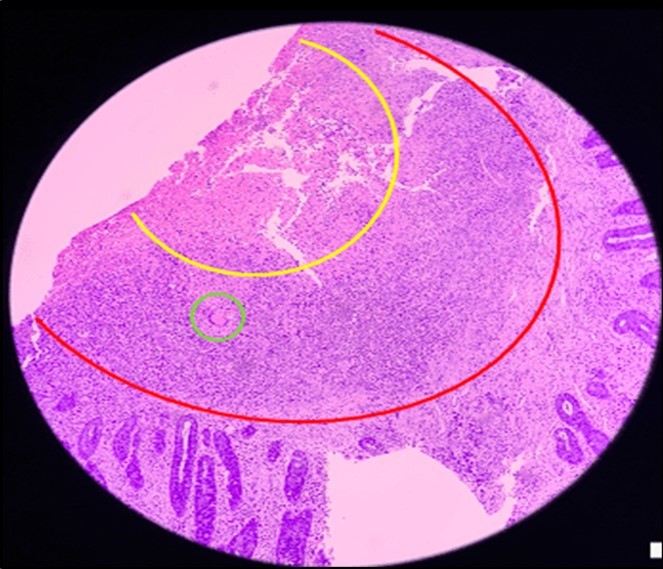

Biopsy showed chronic granulomatous inflammation with caseation necrosis and Langhan’s type giant cells consistent with tuberculous etiology (Figure 6, and Figure 7). TB PCR detected Mycobacterium tuberculosis, Rifampicin (MTB, RIF) resistance indeterminate. Category I Anti-TB treatment for six months was started and the service planned to repeat both colonoscopy and CT-scan after the initial round of anti-TB treatment. Currently, the patient is able to work with no abdominal pain and was able to tolerate her anti-TB drug regimen

Figure 6.Pathologic slide in the low power field. The area inside the yellow circle is the area of central necrosis. The portion inside the red circle is the peripheral lymphocytic ring, and inside the green circle is the Langhan’s type multinucleated giant cells